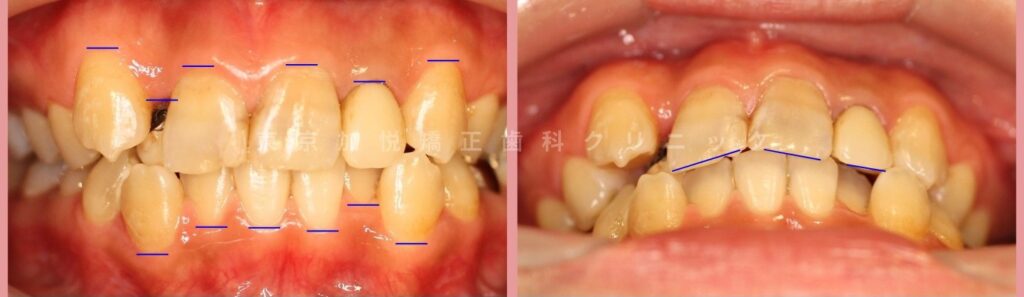

歯が歯列よりも舌側にずれる「舌側転移」や噛み合わせに参加しない歯「八重歯」などがみられました。

▼写真左:正面写真。歯ぐきと歯の間に目印

写真右:正面やや下方からの写真。歯の切端に目印

前歯の重なりがとれ、審美性が高まりました

19ヶ月間の表側矯正を行いました。

▼サイドからみら治療前後写真。写真内青線の部分が1歯に対して2歯で咬み合うようになり、奥歯の噛み合わせも大きく改善されました。

▼写真内にある目印の位置関係のバランスがとれ、審美的に大きく改善されました。前歯のかさなりももちろんとれ、清掃性が高まりました。